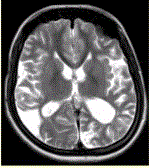

问题 女性,22岁。癫痫发作及智力异常。MRI显示见下图。 关于该病描述正确的是

选项 A.脑萎缩 B.双侧顶枕叶软化灶 C.蛛网膜囊肿 D.双侧顶枕叶脑梗死 E.脑积水 F.脑炎

答案 AB